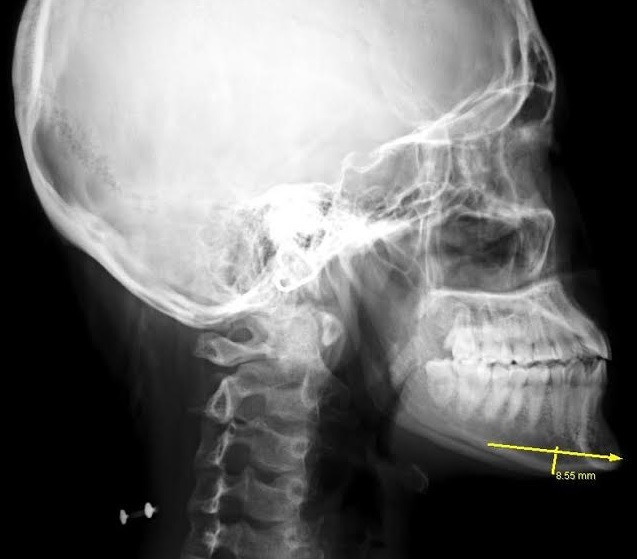

20代女性、顎が長いこと、

しゃくれていることを気にされ

顎骨切りの適応にて手術を行いました。

正面視では下口唇からオトガイ先端までの距離が長く、

フェイスラインも比較的細いため、

中央を大きめに切除し、

やや発達気味の左側を大きめで切除します。

下顎の前突(しゃくれ)については骨きりの際、

大部分が切除でき、残りはサージカルモーターで

削ることにしました。

切除できた骨片は、

横幅6.3cm 最大厚 左9mm 右8mm 中央6mmで

今回もほぼデザインどおりの切除が行えました。